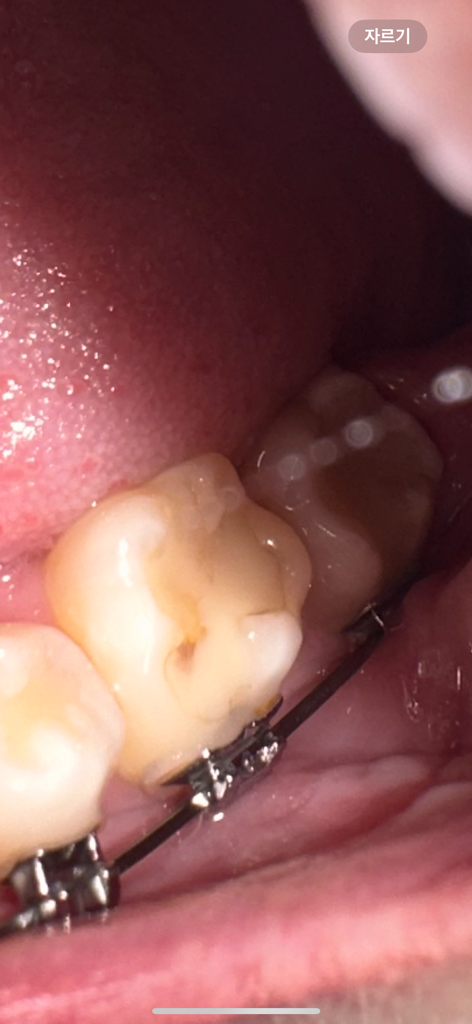

기존에 떼웠던 치아에 대해 이차충치를 의심하시는 것 같습니다. 이차충치의 경우 좀 더 명확한 증상이 확인되면 좋습니다. 뜨거운 것, 차가운 것을 먹었을 때 불편한 증상이 대표적입니다.

치과에서는 떼운 재료 하방의 치아 상태를 확인하기 위해 방사선 사진을 찍고요, 이상이 생겼다면 충치치료를 하거나 충치가 아주 깊으면 신경치료의 가능성도 있습니다.

교정치과 외의 일반치과에서 충치치료를 해도 상관없으나 만약 신경치료까지 해야 하는 경우 치아에 대한 처치가 교정에 영향을 미칠 수도 있으므로 교정치과와 논의해보는 것이 좋습니다.